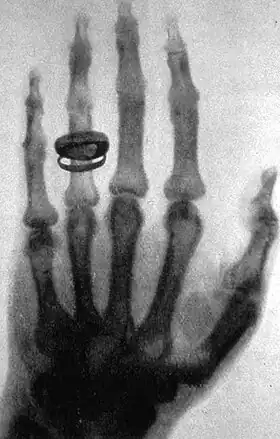

![]() X-ray of a hand. X-rays are a common medical test. | |

- Radiologic tests, in which, for example, x-rays are used to form an image of a body target. These tests often involve administration of a contrast agent.